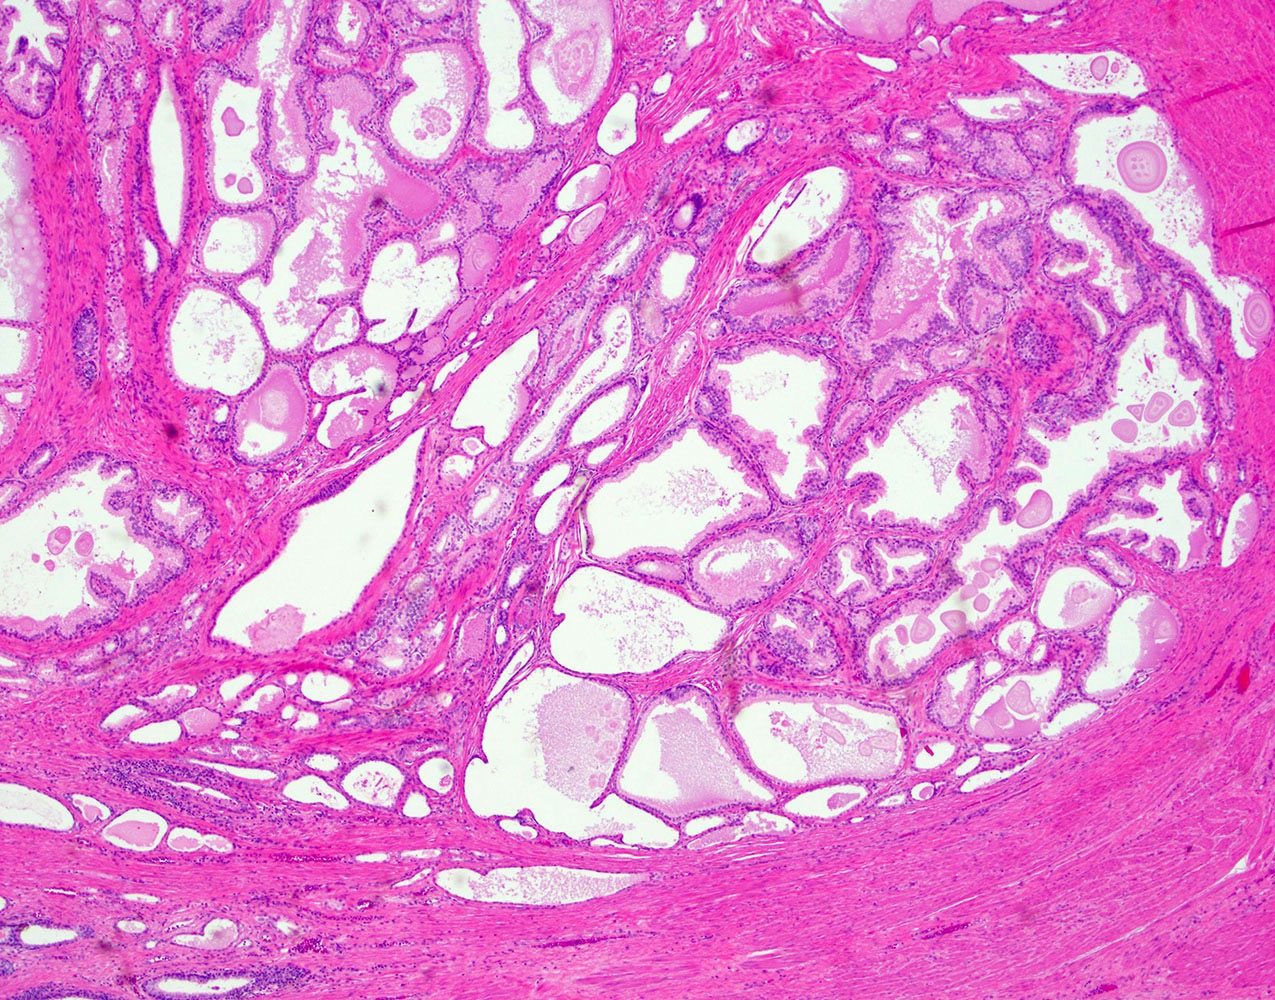

- 1Nodular hyperplasia of glands and stroma in transitional zone

- 2Cystically dilated glands with papillary infoldings

- 3Double-layered epithelium (basal + luminal)

- 4Corpora amylacea in gland lumens

- 5Stromal component: smooth muscle and fibrous tissue

Benign Prostatic Hyperplasia (BPH) is non-neoplastic proliferation of both glandular and stromal elements in the periurethral transitional zone of the prostate, driven by dihydrotestosterone (DHT). Histologically it features enlarged glands with papillary projections lined by double-layer epithelium (inner columnar + outer cuboidal basal cells) and cystic dilation.

- Cystic glandular spaces with papillary projections into the lumen

- Double-layer epithelium: inner tall columnar secretory cells + outer cuboidal basal cells

- Corpora amylacea: laminated eosinophilic concretions in gland lumens

- Increased fibromuscular stromal component